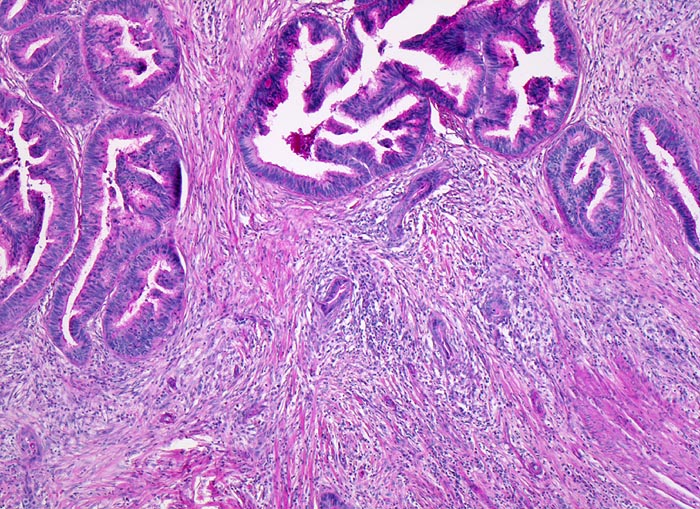

• Tumordrüsen infiltrieren Submukosa und Muscularis propria der Kolonwand (Infiltration der Muscularis propria=pT2).

• Die Karzinomdrüsen sind teilweise umgeben von zellarmem desmoplastischem Stroma und einem dichten gemischten Entzündungsinfiltrat.

• Ektatische Tumordrüsen sind gefüllt mit nekrotischem Zelldetritus.